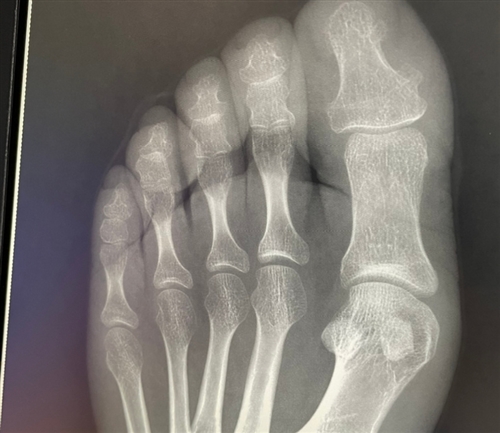

7、又开始倒霉,我服了,跆拳道课踢板子把脚踢骨折了。一拍片子还真是骨折。

11、是不是就我骨折脚肿了好多地方都像个鸡蛋一样大小啊,真的越肿越大,从一个小包变成整个脚板都肿,还带着紫红淤血。

18、人生中第一次骨折希望也是最后一次太痛了,脚都肿了。

22、又骨折了外面吃饭崴了下脚就骨折了,补钙啊!家人们。

26、把脚崴了去医院看结果骨折了,绑着石膏真的哪哪不方便,问题是之后上学还要天天拄拐杖。